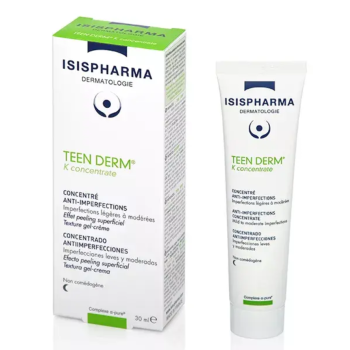

Véritable soin SOS grâce à sa forte concentration (dose maximale autorisée en cosmétique), il réduit les boutons naissants ou installés sur le visage en seulement quelques jours. | Isispharma Teen Derm K Concentrate Concentré Anti-Imperfections 30ml est un soin de nuit qui s'adresse aux peaux mixtes à grasses afin de diminuer les imperfections et réguler l'excès de sébum. | Le soin réparateur apaisant boréade R noviderm ACM hydrate, répare et apaise les peaux irritées et desséchées. | Effaclat duo (+) unifiant soin teinté La Roche-posay est un soin teinté anti-imperfections correcteur désincrustant anti-marques. | Ce soin global « tout en un » favorise l’élimination des imperfections cutanées, unifie naturellement le teint et limite l’apparition des marques liées au soleil. | Le Gel SOS asséchant HYSEAC est un soin local SOS "effet patch invisible" à utiliser tout au long de la journée. | Hyséac Sérum peau neuve Booster anti-imperfections 30 ml est un sérum anti-imperfections pour les peaux adultes à tendance acnéique. |